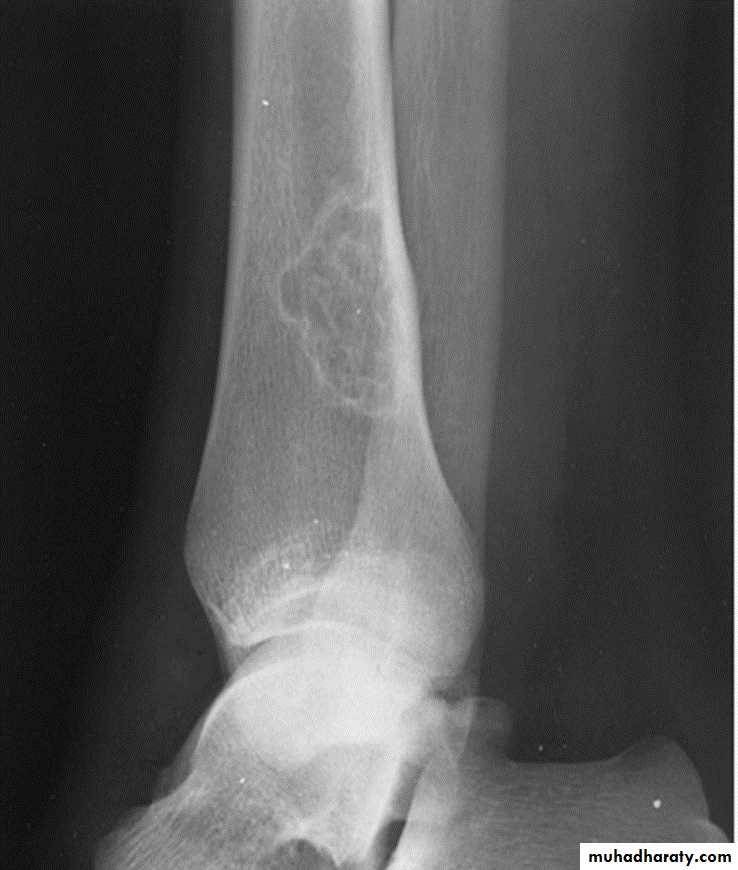

Osteochondroma of the distal femur.

The cortex is continuous with that of the underlying bone and trabecular bone merges with that of the femur. A well-defined cartilage cap contains calcification and is directedaway from the joint.